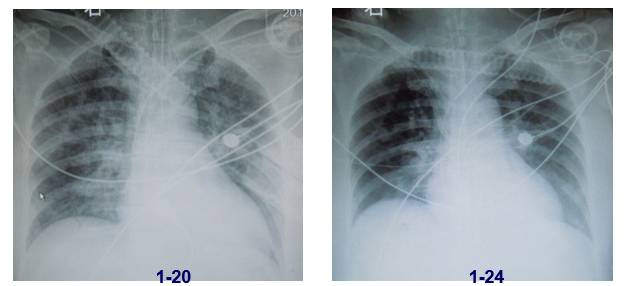

1.24痰培养 白色假丝酵母样菌

治疗调整

病情转归

患者最终病情恶化考虑感染加重